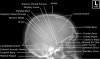

4. Adult Skull - Lateral View